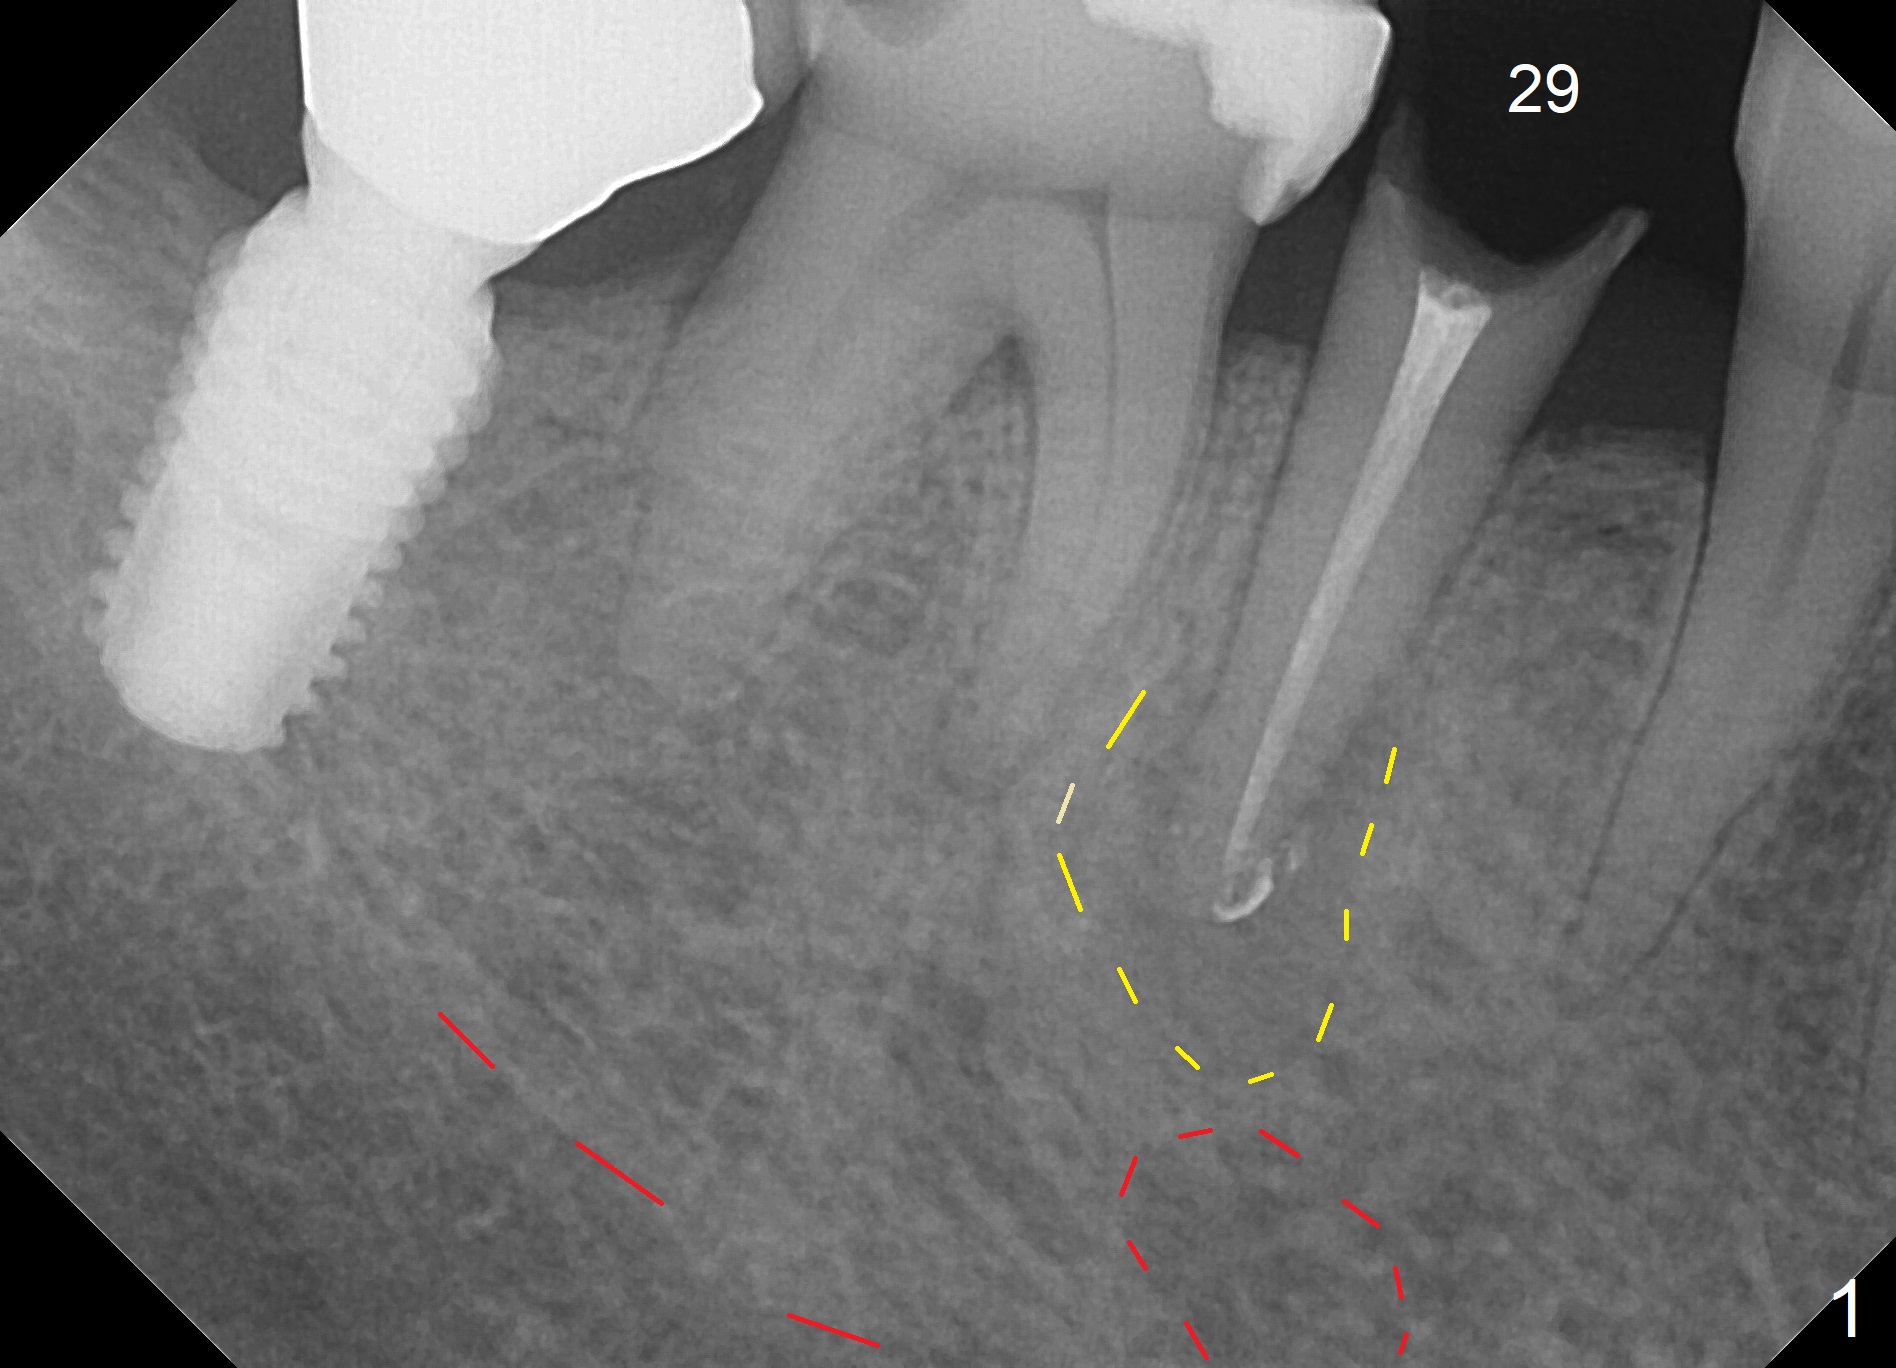

A 67-year-old woman fractures the tooth #29 three months post RCT. There is persistent periapical radio-lucency (Fig.1 yellow dashed line), which is close to the Mental Loop (red dashed line). Since the root of the affected tooth deviates distal, osteotomy will be established mesial (Fig.2). To reduce the chance to injury the buccally located loop, the osteotomy should be as lingual as possible. Initial depth will be 15 mm (shy of the Loop, bone level, 18-19 mm gingival level) with 2 mm drill, followed by the marked parallel pin. If primary stability cannot be achieved, place a long implant as indicated in Fig.2 as long as the osteotomy remains lingual.